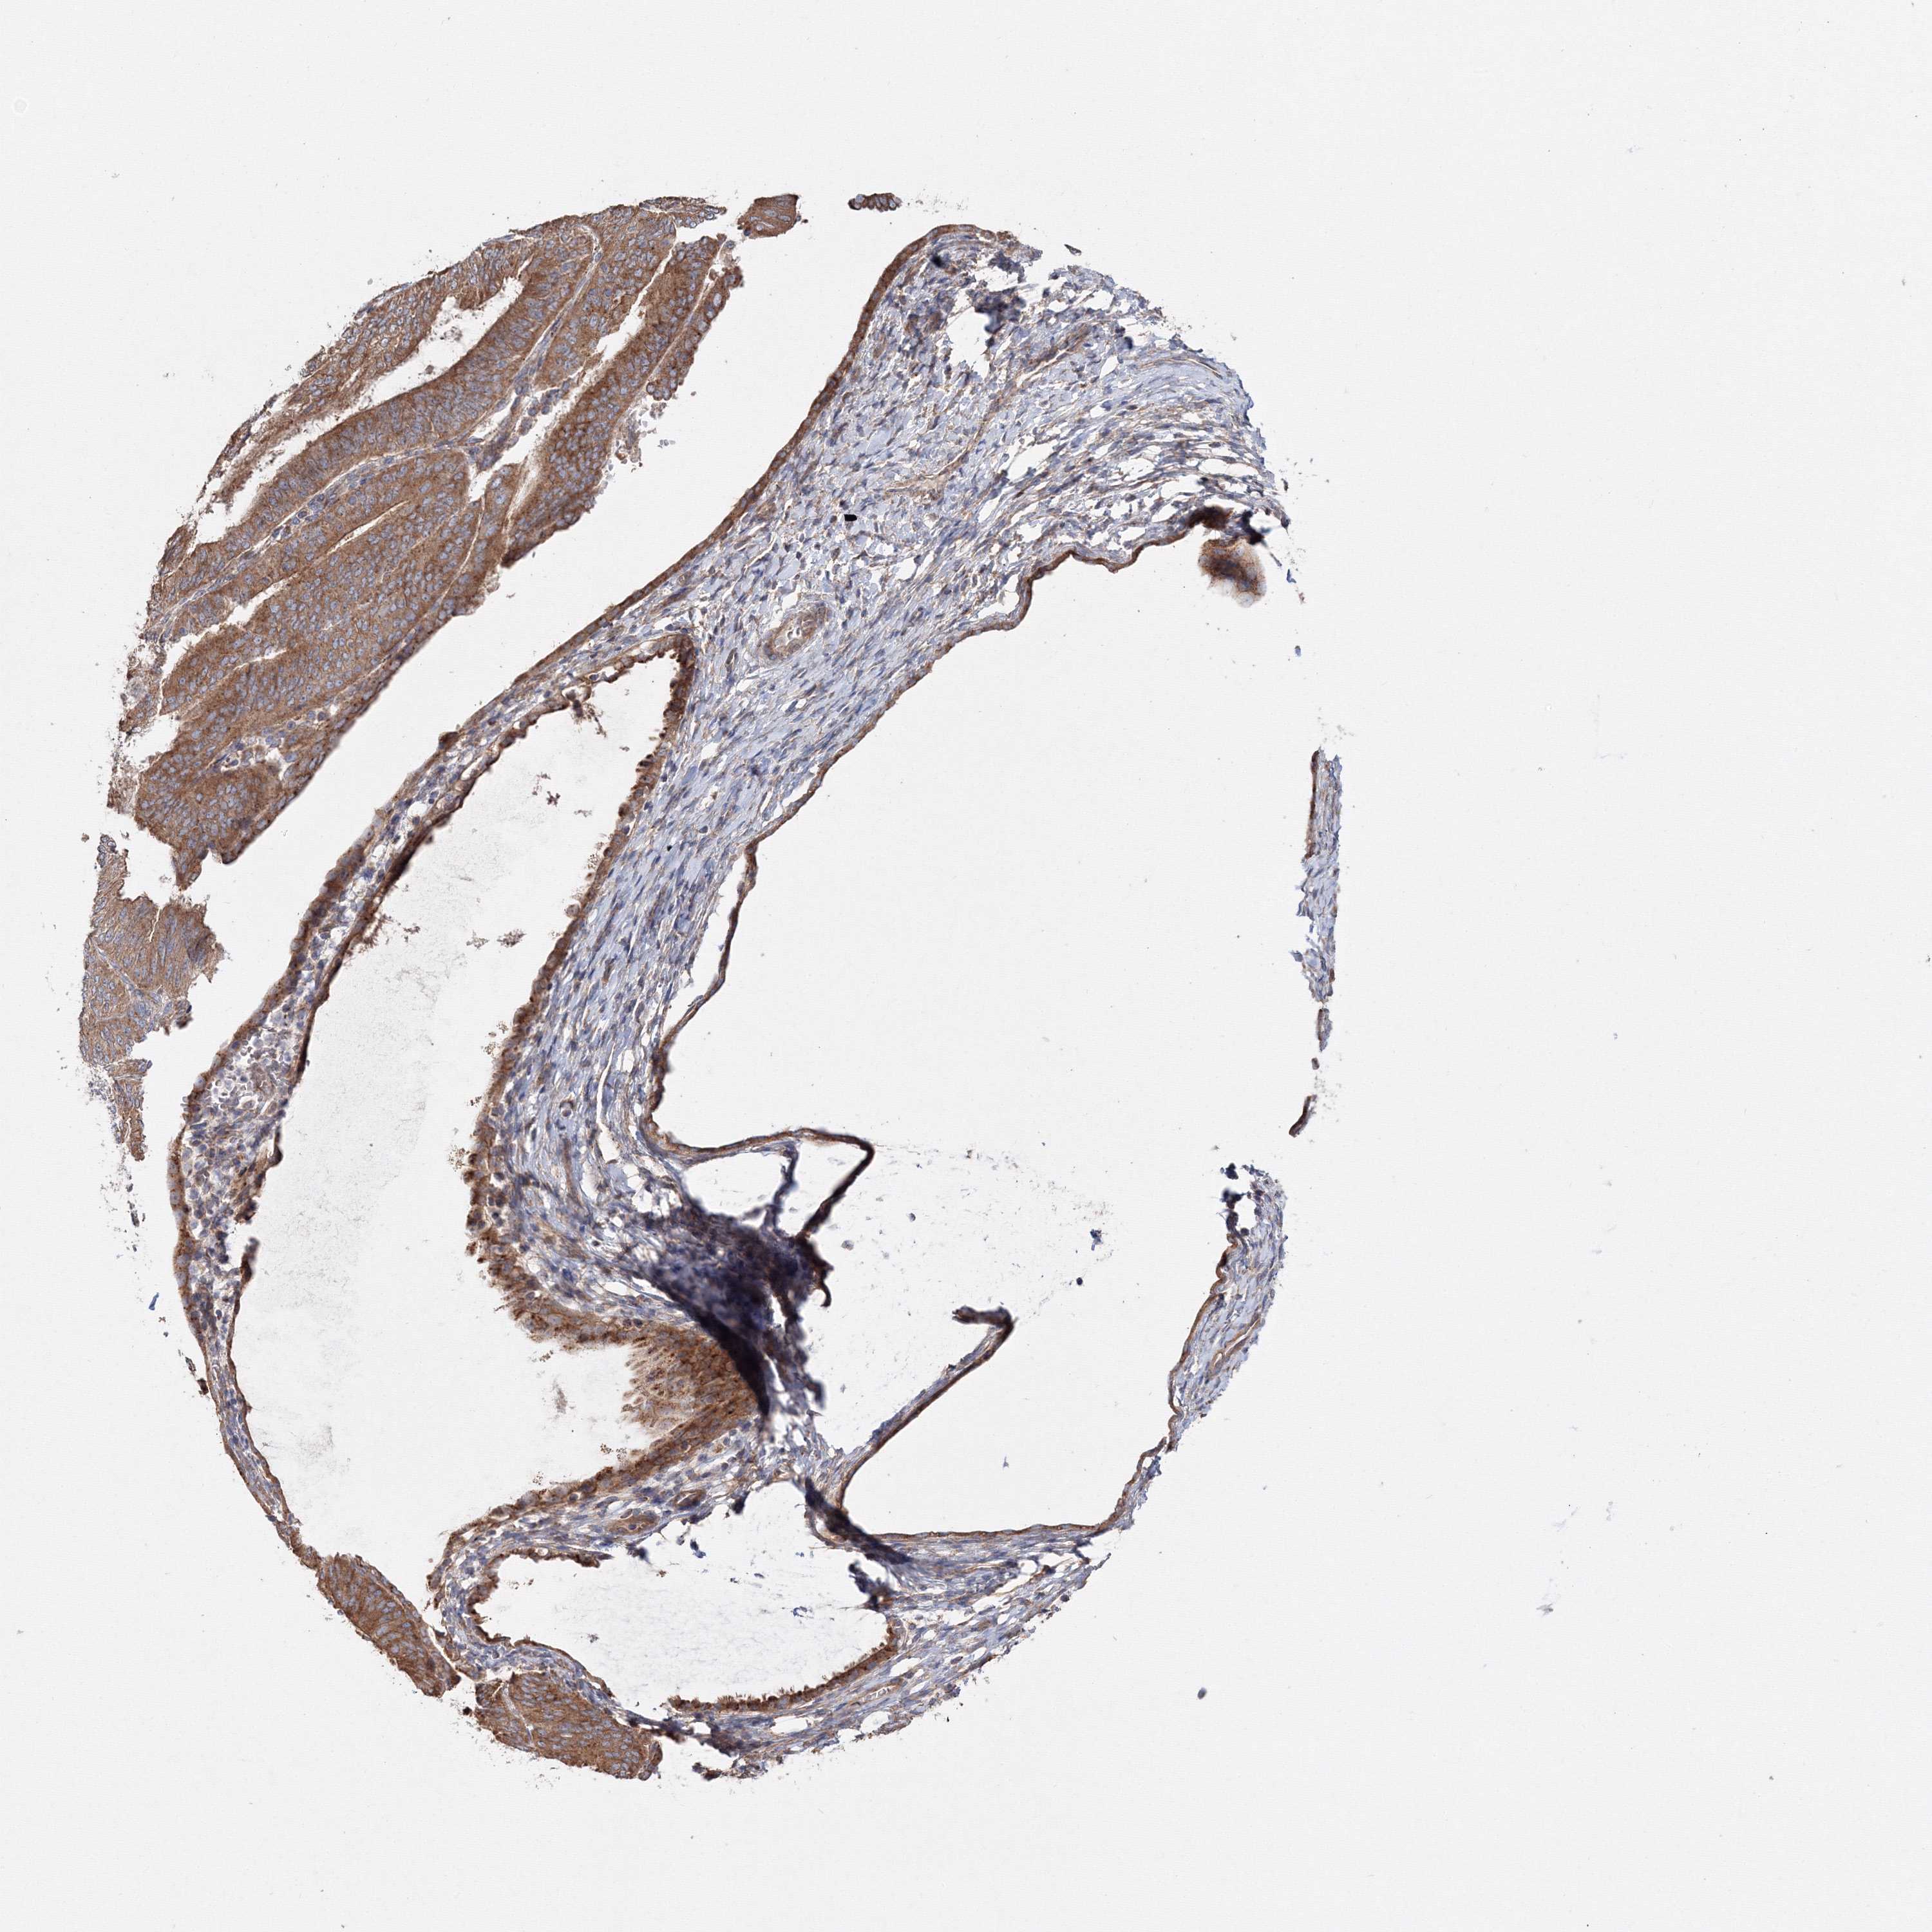

ENDOMETRIAL CANCER - Protein expressioni

A mouse-over function shows sample information and annotation data. Click on an image to view it in a full screen mode. Samples can be filtered based on level of antibody staining by selecting one or several of the following categories: high, medium, low and not detected. The assay and annotation is described here.

Note that samples used for immunohistochemistry by the Human Protein Atlas do not correspond to samples in the TCGA dataset.

Antibody stainingi

Antibody staining in the annotated cell types in the current human tissue is reported as not detected, low, medium, or high, based on conventional immunohistochemistry profiling in selected tissues. This score is based on the combination of the staining intensity and fraction of stained cells.

Each image is clickable and will lead to virtual microscopy that enables deeper exploration of all samples and also displays staining intensity scores, fraction scores and subcellular localization as well as patient and tissue information for each sample.

Antibody HPA037525

Antibody HPA037526

Staining

High

Medium

Low

Not detected

Intensity

Strong

Moderate

Weak

Negative

Quantity

>75%

75%-25%

<25%

None

Location

Nuclear

Cytoplasmic/membranous

Cytoplasmic/membranous,nuclear

Adenocarcinoma, NOS

Adenoma, NOS